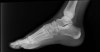

X-ray 사진을 찍으면 종골 후방의 골단핵에 경화상이나 분절상을 보입니다.

X-ray : 종골 골단염(Sever's disease)